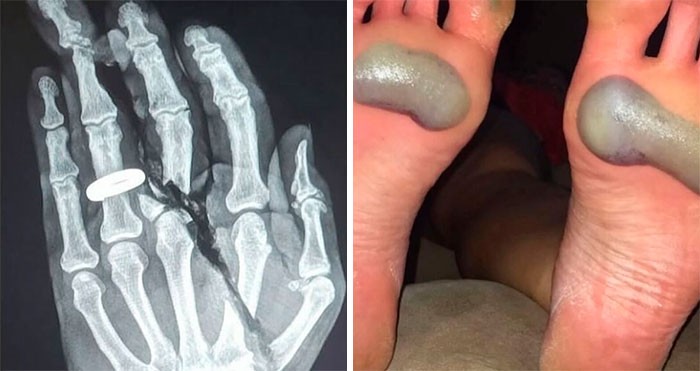

30 zdjęć medycznych, które dowodzą, iż ciało jest ...